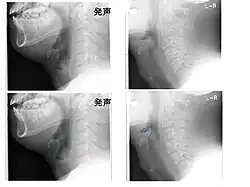

Left column: Normal epiglottis. Right column: Epiglottitis. -

On lateral C-spine X-ray, the thumbprint sign describes a swollen, enlarged epiglottis.[11] A normal X-ray, however does not exclude the diagnosis.[11] An ultrasound may be helpful if specific changes are present, but its use as of 2018 is in the early stages of study.[11]

Diagnosis may be confirmed by direct inspection using a laryngoscope, although this may provoke airway spasm.[15] If epiglottitis is suspected, diagnosis is made on basis of fiberoptic laryngoscopy exam carried out in controlled environment like an operating room.[16][17]